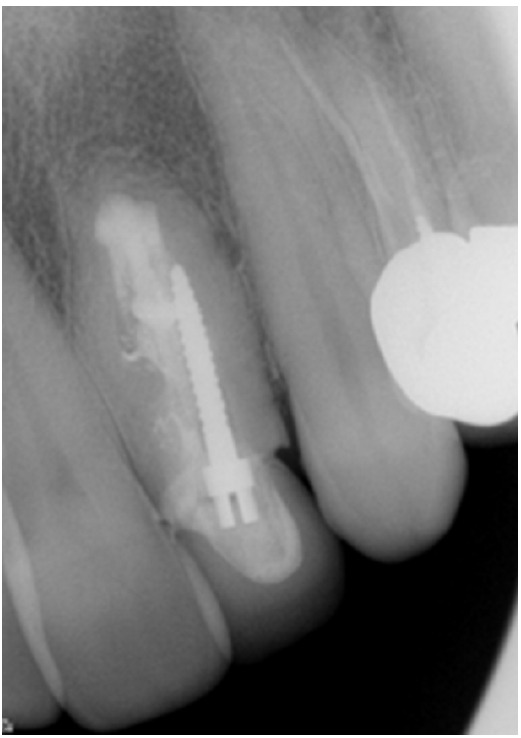

In 2021, when the patient (now aged 63 years) was referred by the treating dentist for evaluation, the tooth was still clinically asymptomatic with normal periapical tissues (Figure 4). The patient did not attend any follow-up appointments after 2021, despite multiple attempts to contact and recall her. A summary of events and outcomes is presented in Table 1.